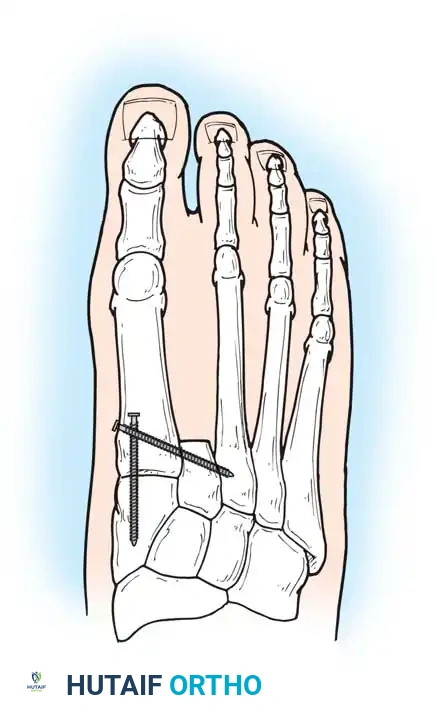

Surgical Warning: To prevent severe hallux valgus following a second ray amputation, Smith recommended a complete second ray resection combined with surgical narrowing of the foot using transverse screw fixation between the first and third metatarsals.

Second ray amputation with screw fixation